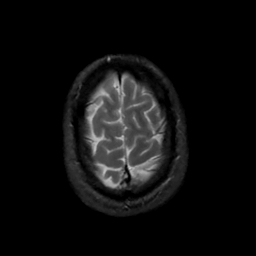

MR Study #10, April 28, 1991 -- Slice #44

[Home][Help][Clinical][Tour 1][Tour 2] Slice 44